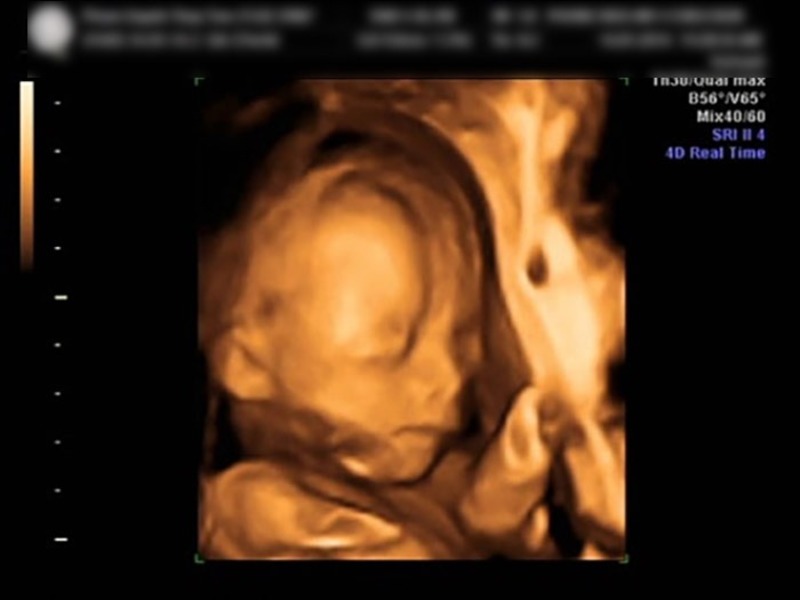

Siêu âm 5D (5 Dimensions) là phiên bản nâng cấp của siêu âm 4D, kết hợp hình ảnh 3D động với công nghệ ánh sáng và bóng đổ hiện đại, tạo ra hình ảnh sắc nét, màu sắc tự nhiên và chân thực hơn. Siêu âm 5D không chỉ cho bố mẹ trải nghiệm như “nhìn thấy con thật” mà còn giúp bác sĩ phát hiện các dị tật bẩm sinh tinh vi hơn nhờ chất lượng hình ảnh cao.

Đặc điểm nổi bật của siêu âm 5D:

• Hình ảnh cực kỳ sắc nét, màu da và biểu cảm của bé rõ ràng, chân thực.

• Khả năng hiển thị chi tiết các cấu trúc giải phẫu của thai nhi giúp chẩn đoán chính xác hơn.

• Cải thiện chất lượng hình ảnh ngay cả trong môi trường nước ối ít hoặc vị trí thai khó quan sát.

• Mang đến trải nghiệm sống động cho bố mẹ khi ngắm bé yêu.